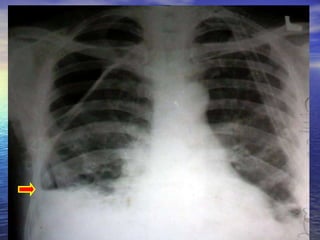

30 YEAR OLD MALE CAME TO OPD WITH COMPLAINTS OF BREATHLESSNESS 1 MONTH DURATION. NOW INCREASED FOR 2 DAYS H/O COUGH WITH EXPECTORATION 1 MONTH CHRONIC ALCOHOLIC AND SMOKER 15 YEARS

CHEST X RAY PA VIEW ADEQUATE INSPIRATION CENTRING, PATIENT POSITION -  NORMAL EXPOSURE/PENETRATION -  ADEQUQTE TRACHEA POSITION -  MIDLINE HEART AND MEDIASTINUM –  NORMAL PLEURAL SPACE  –  HYDROPNEUMOTHORAX  ON THE LEFT SIDE  EVIDENCED BY THE CONVEX  OUTSIDE BORDER OF  LUNG WITH VISCERAL PLEURA AND AIR FLUID LEVEL ? BULLAE/ ?LOCULATED HYDROPNEUMOTHORAX  SEEN  ON RIGHT SIDE EVIDENCED BY CONVEX INWARDS  MARGINS OF THEIR WALLS WITH AIR FLUID LEVEL COSTOPHRENIC ANGLES  BLUNTED BILATERALLY  CARDIOPHRENIC ANGLES  FREE HILA DENSITY, POSITION, SHAPE -  NORMAL SOFT TISSUES –  NORMAL BONES-  NORMAL Imp:LEFT HYDROPNEUMOTHORAX  RIGHT BULLOUS DISEASE/HYDROPNEUMOTHORAX WITH ?PLEURAL THICKENING

CHEST X RAYPA VIEW ADEQUATE INSPIRATION CENTRING, PATIENT POSITION - NORMAL EXPOSURE/PENETRATION - ADEQUQTE TRACHEA POSITION - MIDLINE HEART AND MEDIASTINUM – NORMAL PLEURAL SPACE – HYDROPNEUMOTHORAX ON THE LEFT SIDE EVIDENCED BY THE CONVEX OUTSIDE BORDER OF LUNG WITH VISCERAL PLEURA AND AIR FLUID LEVEL ? BULLAE/ ?LOCULATED HYDROPNEUMOTHORAX SEEN ON RIGHT SIDE EVIDENCED BY CONVEX INWARDS MARGINS OF THEIR WALLS WITH AIR FLUID LEVEL COSTOPHRENIC ANGLES BLUNTED BILATERALLY CARDIOPHRENIC ANGLES FREE HILA DENSITY, POSITION, SHAPE - NORMAL SOFT TISSUES – NORMAL BONES- NORMAL Imp:LEFT HYDROPNEUMOTHORAX RIGHT BULLOUS DISEASE/HYDROPNEUMOTHORAX WITH ?PLEURAL THICKENING